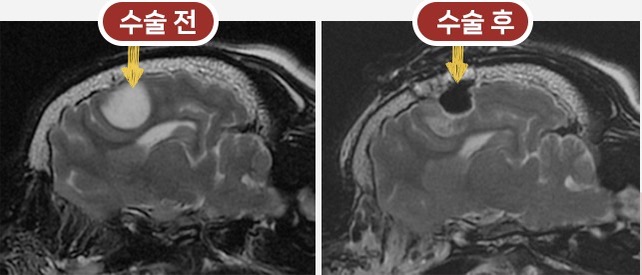

뇌수술 전후 MRI 비교 이미지

MRI 기반 정확 진단

반려동물의 뇌종양을 정확하게 평가하기 위해 사용되는 핵심 영상 진단 장비입니다.

MRI는 뇌 조직의 미세한 구조와 병변을 고해상도로 촬영할 수 있어, 종양의 위치·크기·경계는 물론 주변 신경 조직과의 관계까지 정밀하게 확인할 수 있습니다. CT나 X-ray로는 구분이 어려운 연부조직 변화까지 확인할 수 있어, 종양의 종류를 감별하고 수술 가능 여부접근 방향을 판단하는 데 중요한 기준이 됩니다.